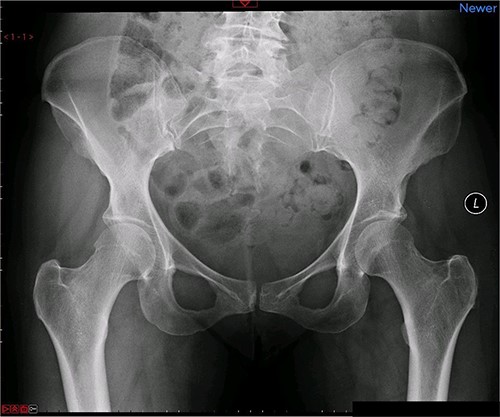

A magnetic resonance imaging (MRI) scan performed in October 2013 (Fig. 1) identified non-compressive, degenerated discs at L4/5 and L5/S1 vertebral levels. However, clinically as the patient was more tender over the left SI joint and the pubic symphysis (Fig. 2), a left sacroiliac joint fusion and symphysis pubis plating procedure was performed in August 2014 (Fig. 3). Following a short period of relief, the pain returned. Subsequently, the patient underwent a 360° fusion (front and back) of the L4/L5 and L5/S1 discs in August 2015 (Fig. 4), a year following the previous surgery. Once again, following a brief period of relief, the symptoms returned. The assumption then was that the initial fusion of the left sacroiliac joint had failed. Therefore, a revision fusion of the left sacroiliac joint and a primary fusion of the right sacroiliac joint was undertaken in August 2017 (Fig. 5).

Preoperative X-ray of the pelvis: preoperative X-ray of the pelvis, performed in March 2014, showing no implants yet in place.